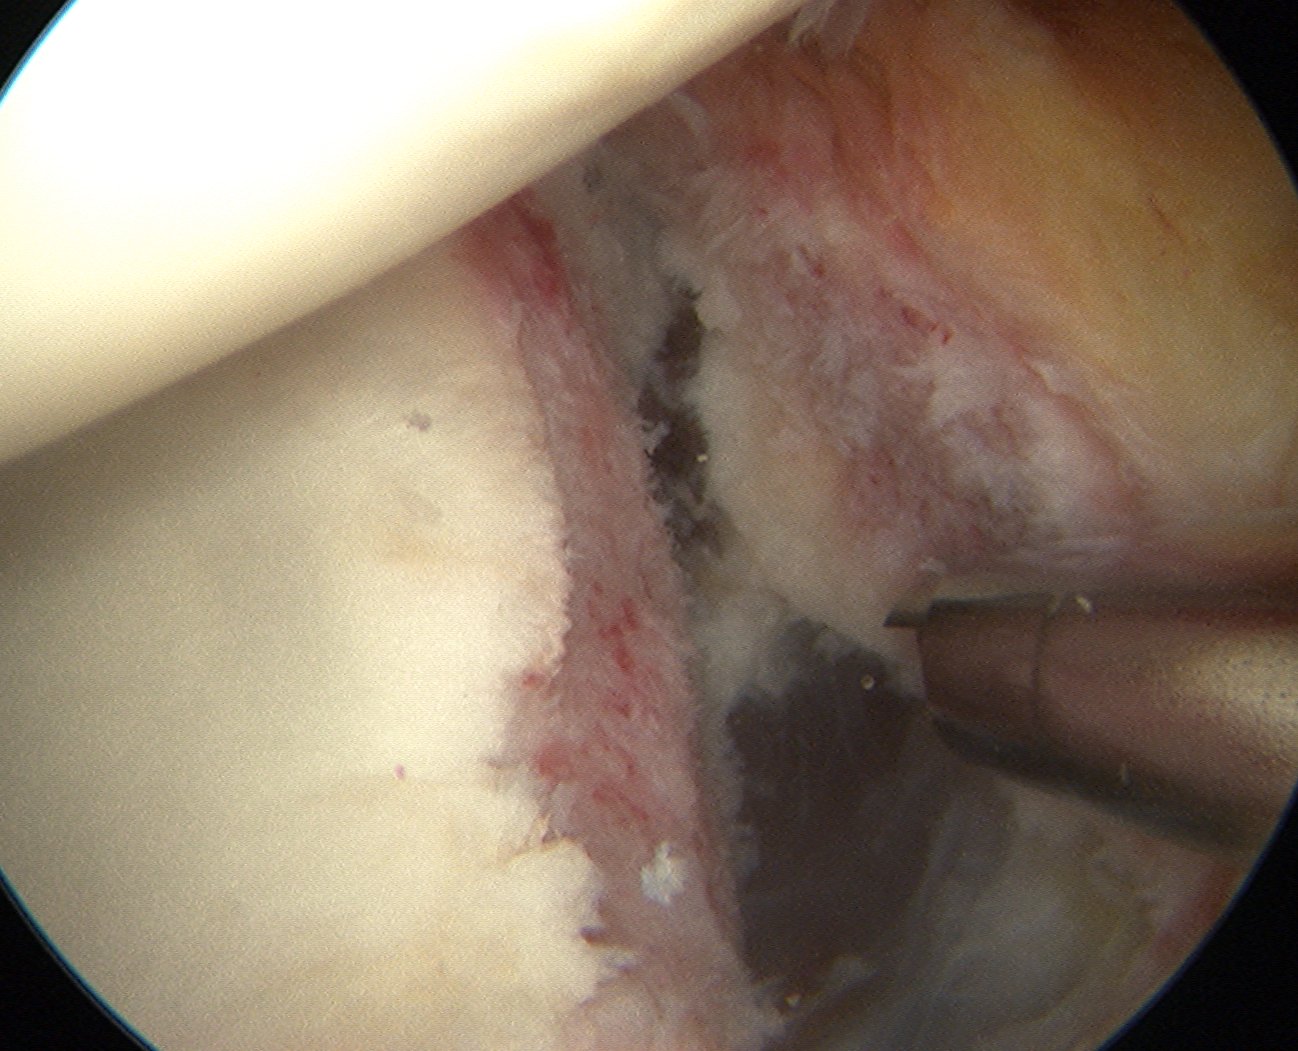

Mobilize labrum

Shoulder Scope Bankart RaspShoulder Stabilisation Labral Mobilisation

Labral mobiliser / rasp

- labral tear can be obvious, but may have partially healed or healed medially

- change camera to anterosuperior portal for better view

- mobilize until can see subscapularis muscle underneath

- need to be able to advance labrum medially and superiorly for repair

Shoulder Arthoscopy Bankart MobilisationShoulder Scope Bankart Mobilisation

Shoulder Stabilisation Anterior Labral MobilisationShoulder Stabilisation Anterior Labral Mobilisation 2